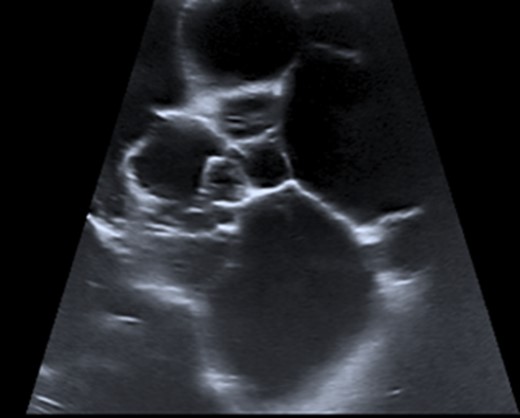

He underwent ultrasonography of his testes which showed a large left sided cystic area 16.6 × 8.2 × 8.8 cm3 with multiple septations and hyperechoic areas (Fig. 1). An epididymal cyst or hydrocele was initially suspected by radiology and further imaging was performed. Inflammatory change was seen in his left inguinal region on computerized tomography and he underwent left radical orchiectomy.

Ultrasonography of paratesticular lesion showing hyperechoic cystic regions with multiple septations.